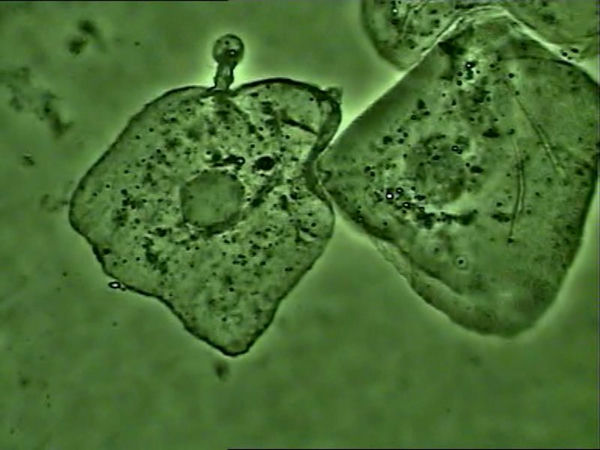

支原體感染的細(xì)胞

支原體主要黏附在細(xì)胞膜上生存,使用光學(xué)顯微鏡高倍相襯觀察,如果看到細(xì)胞核周圍大量靜止或布朗運(yùn)動(dòng)的小黑點(diǎn),可以推斷大概率為支原體。